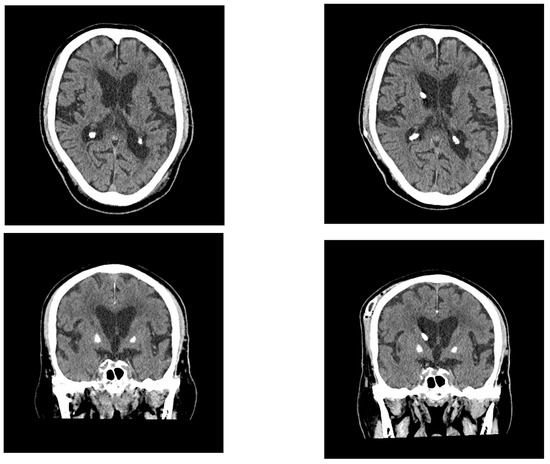

2.1. Case 1